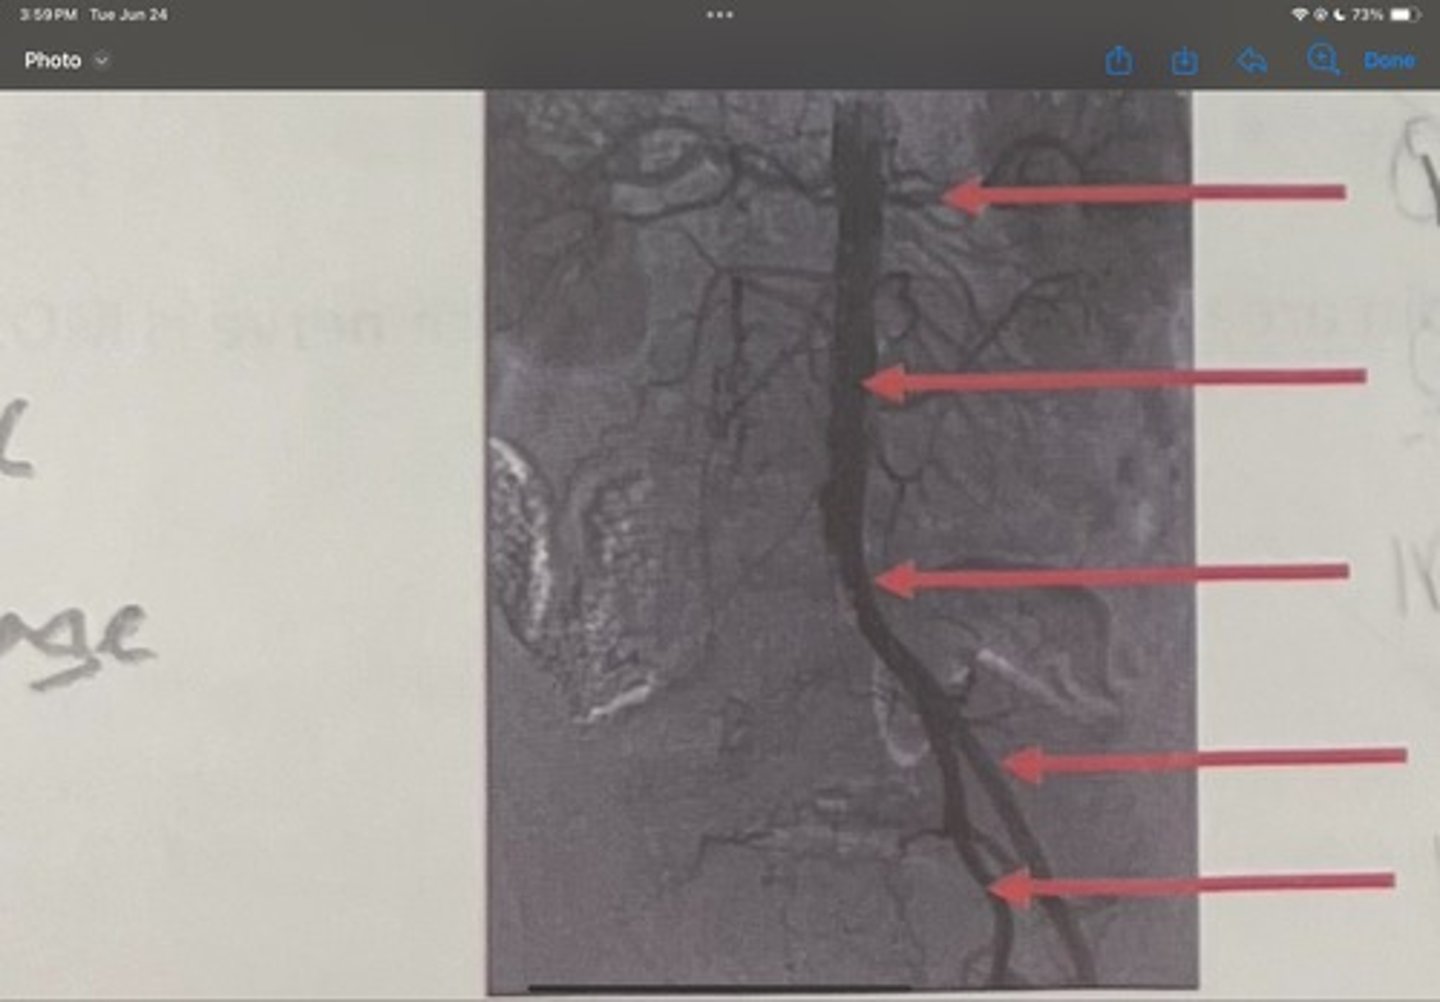

Renal artery

What is the 1st one

Abdominal aorta

What is the 2nd one

Common iliac artery

What is the 3rd one

External iliac artery

What is the 4th one

Internal iliac artery

What is the 5th one

right common iliac artery blockage

What is the pathology of the image